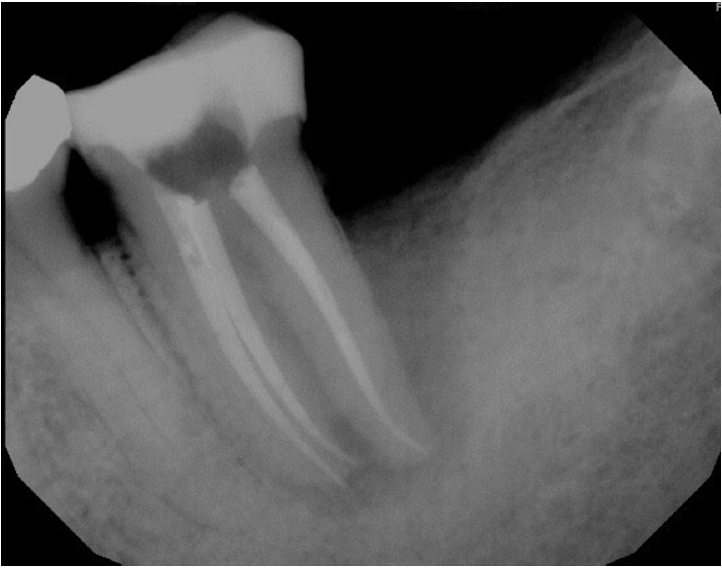

Working lengths were determined using an electronic apex locator (RootZX; J Morita, Kyoto, Japan) and confirmed with a periapical radiograph, which also showed a radiopaque fragment consistent with a cemental tear (Figure 2). The chamber was flooded with 5% sodium hypochlorite, and the canals were instrumented using size 8, 10, 15, and 20 K files, followed by a 25/.07 Primary Wave One Gold (Dentsply Sirona, Charlotte, NC, USA) reciprocating file. Irrigation was performed with 12 mL of 5% sodium hypochlorite with ultrasonic activation for 30 seconds per canal. Calcium hydroxide was placed as an intracanal medicament with a lentulo spiral, and the tooth was temporized with a sterile sponge and Cavit (3M ESPE, St. Paul, MN, USA). The patient was informed to return in 2 weeks for completion of the root canal.

Figure 2.

Working length radiograph showing radiopaque fragment consistent with a cemental tear along distal root (red arrow).